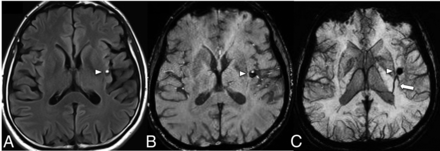

A middle-aged patient with new-onset ataxia. T1WI (A) and SWI MIP (B) show a CCM in the right superior cerebellar peduncle (arrowheads) and a large left cerebellar DVA with the collector vein (arrow) draining into the transverse sinus. Quantitative susceptibility mapping (C) analysis of the CCM shows a high mean susceptibility value of 858 parts per billion (with threshold). An ROI with a red boundary represents the exclusive object boundary, and the purple area represents thresholded pixels (150 parts per billion). SWIM (Siemens) parameters: TE = 20.00 ms; TR = 27.00 ms; flip angle = 150; resolution = 0.937 × 0.937 ×2.5 mm. Images courtesy of Dr E. Mark Haacke.